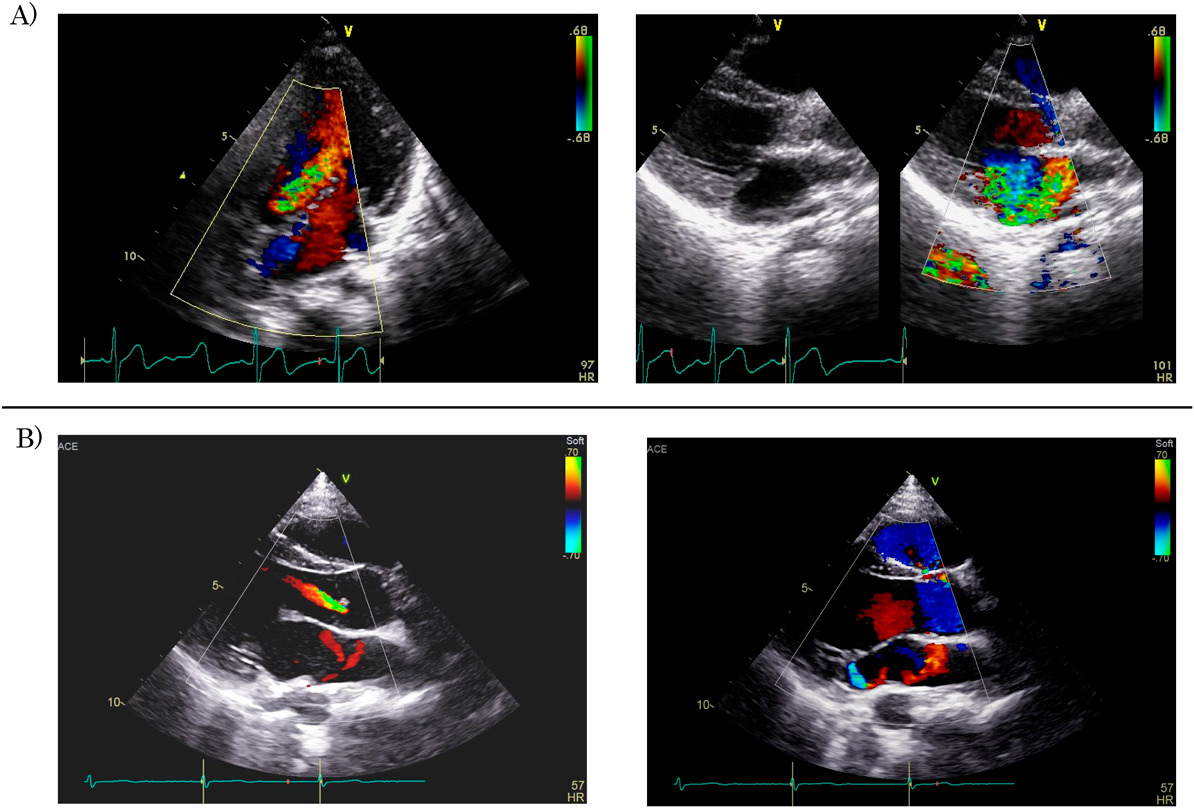

Fig. 2 Color Doppler echocardiograms of case 1

A) Color Doppler echocardiograms of case 1 on admission, showing severe aortic regurgitation (AR) on the 5-chamber view (left panel) and severe mitral regurgitation (MR) on the left ventricular long axis view (right panel). Left ventricular end-diastolic dimension (LVEDD) and ejection fraction (LVEF) were 44.2 mm (148%N) and 78.5%, respectively. B) Color Doppler echocardiograms of case 1 recorded 7 years after the onset of rheumatic fever, showing that AR was apparently reduced (left panel), and only trivial MR remained (right panel). LVEDD and LVEF were 43.1 mm (108%N) and 77.2%, respectively.